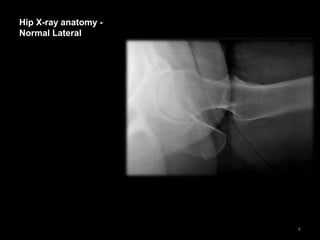

Hip X-ray anatomy -

Normal Lateral

6

• The cortex of the

proximal femur is

intact

• The Lateral view is

often not so clear

because those with

hip pain find the

positioning required

difficult

7